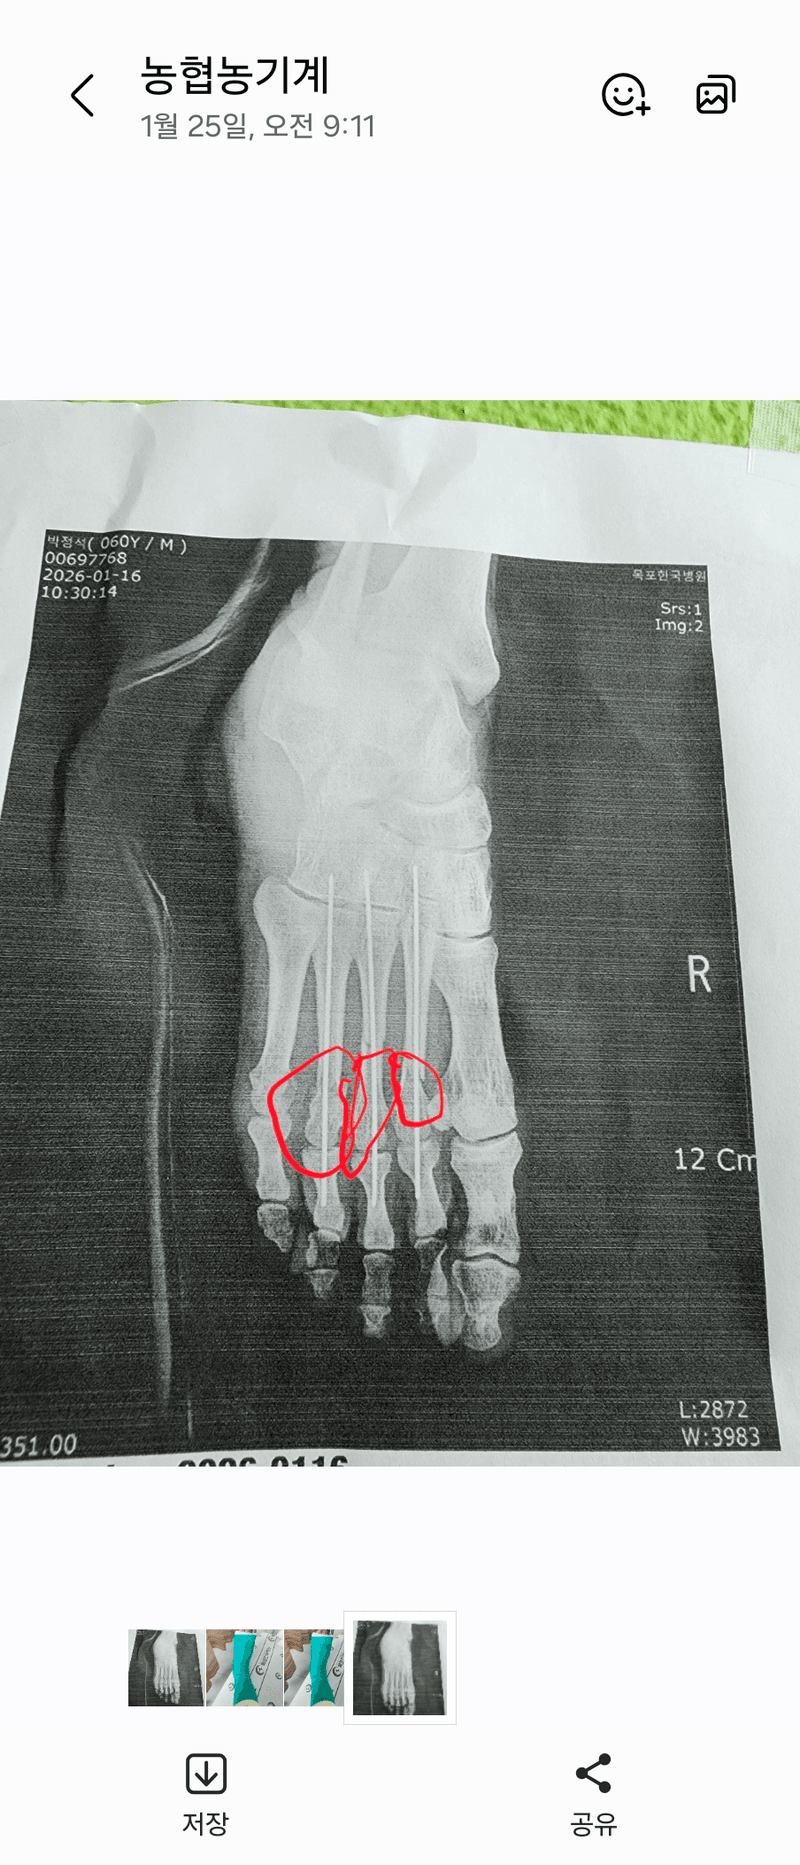

오른발중저골고절로작업불가